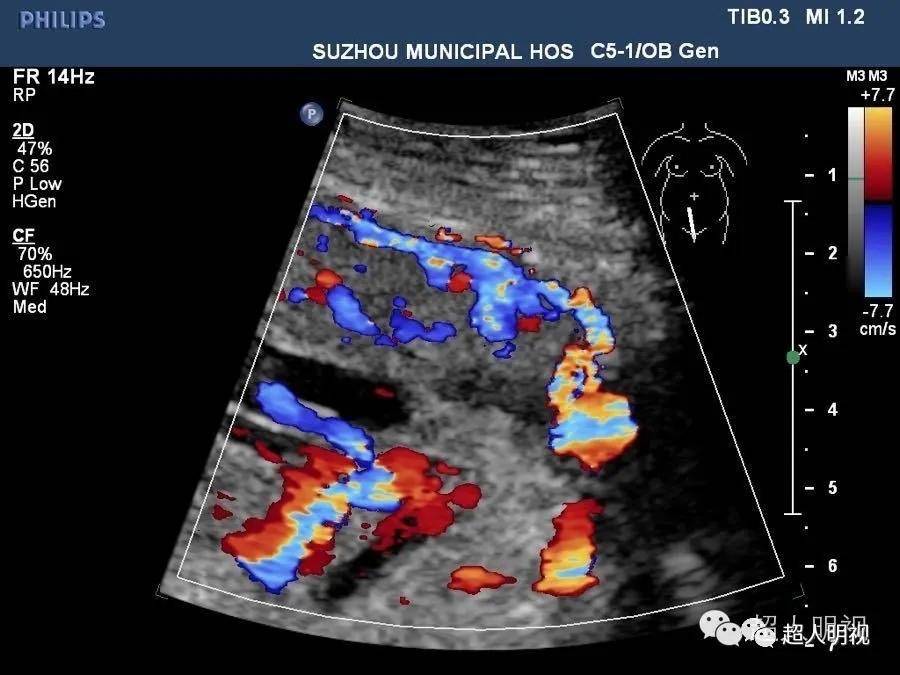

胎盘植入超声诊断

胎盘植入一例